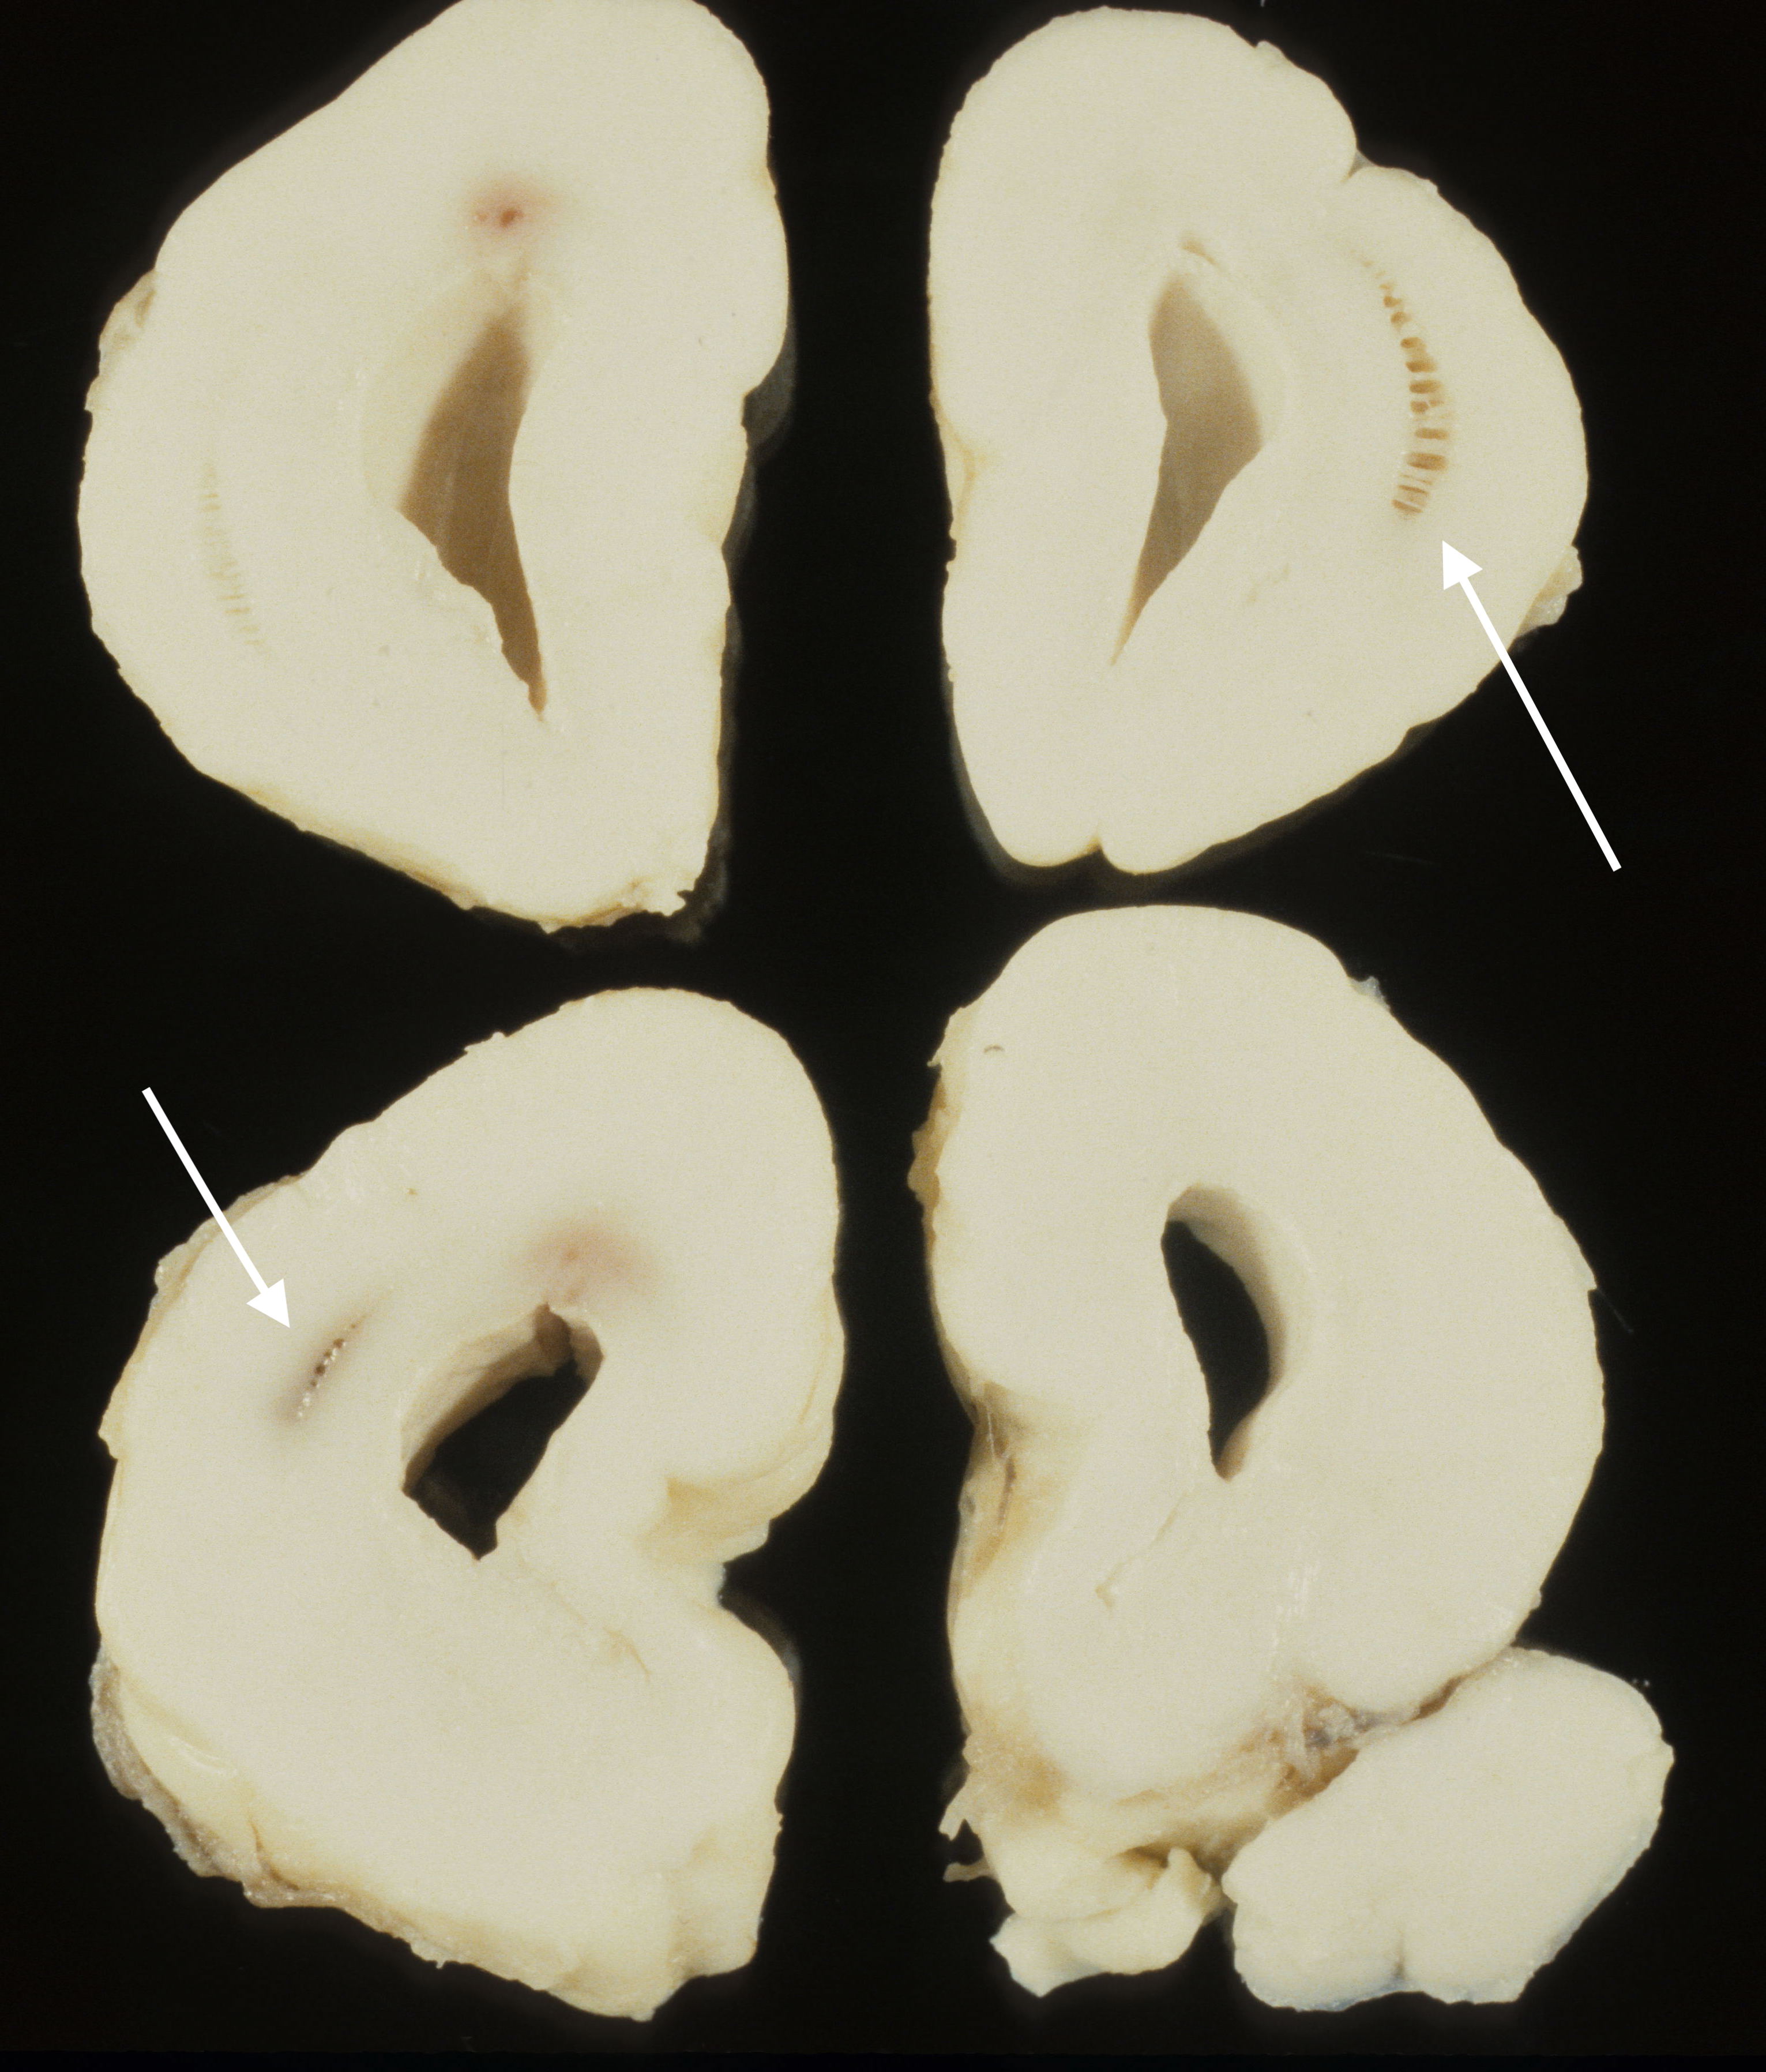

Edema:

Following prolonged experimental hypoxia in monkeys, Dr. Myers discovered that the mechanism of brain injury involved edema from vascular leaking5,6. In the older gestation fetal brain, edema when marked can be recognized as compression of the lateral ventricles (Fig 8). This edema may also increase the expected weight of the brain for a given gestation.